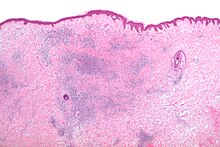

The histomorphologic appearance of insect bites is usually characterized by a wedge-shaped superficial dermal perivascular infiltrate consisting of abundant lymphocytes and scattered eosinophils. This appearance is non-specific, i.e. it may be seen in a number of conditions including:[5]